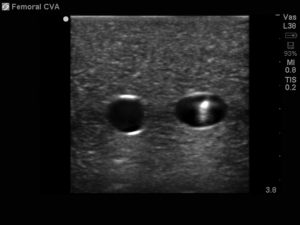

- Ultrasound guided cannulation workshops focus on improving cannulation skills using a portable ultrasound probe.

- Ultrasound cannulation is SUCH A USEFUL SKILL. I used it everyday when I worked in my after hours/ward call rotation.

- The purpose of ultrasound cannulation is to use the ultrasound probe to assist practitioners in inserting peripheral intravenous cannulas into patient’s arms/legs.

- This is especially useful when patients have difficult access for example inpatients in renal medicine, vascular surgery or oncology.

- Ultrasound guided cannulation courses usually involve a theoretical component and a practical component

- The theoretical component involves understanding the principles behind the ultrasound probe and how to get the best view of the vein/artery.

- The practical component involves practicing the skill of inserting a cannula under ultrasound guidance.